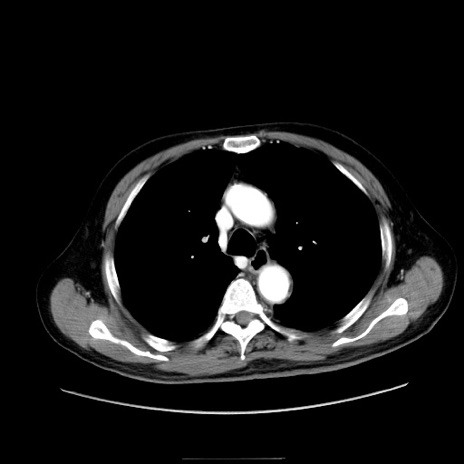

症例30(横断像)

【症例】80歳代男性

【主訴】臍周囲痛

【現病歴】約6時間前から臍下部痛が出現。次第に腹部膨隆・背部痛も生じてきたため来院。背部痛の場所は変化しない。

【身体所見】意識清明、BT 36.3℃、BP  131/87mmHg、P 87bpm、SpO2 100%(RA)、臍周囲自発痛・圧痛あり、反跳痛なし、自発痛部位に一致して板状硬あり、腹部膨隆、腸雑音減弱、CVA tenderness両側陰性。